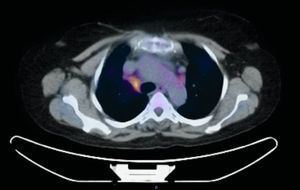

We report the case of a 58-year-old woman with a history of subclavian-jugular deep vein thrombosis in 2014, with secondary pulmonary thromboembolism and pulmonary hypertension not investigated due to refusal of consent by the patient, moderate tricuspid regurgitation and intermittent bronchial asthma. She is a native of Morocco, and last visited the country in September 2013. She lives in an urban environment, and has 2 dogs which are regularly seen by the veterinarian. No other significant epidemiological data, family history, known drug allergies, toxic habits, or occupational exposure were reported. She attended the respiratory medicine department in February 2015, referred by her primary care physician, 6–8 weeks after onset of a clinical picture of dysthermia, with undocumented fever, dyspnea on moderate exertion, cough with sparse, thick, whitish expectoration, loss of appetite, and asthenia. Physical examination revealed mild tachypnea, septic mouth with several teeth missing, no mouth ulcers, rhythmic heart sounds with no murmur, and generally reduced breath sounds with fine crackles in both lung bases. No other data of interest. Laboratory tests showed a slight increase in C-reactive protein and mild leukocytosis. No pathological findings were reported in repeat sputum samples (sputum smear and culture). Chest radiography showed general cardiomegaly and right basal interstitial-alveolar infiltrate. Chest computed tomography (CT) showed bilateral hilar and mediastinal lymphadenopathies of significant size, the latter in the lower paratracheal and subcarinal region, and alveolar infiltrate in the right lower lobe. Given the CT findings, a positron emission tomography (PET) study was performed, which confirmed increased metabolism in the lower right paratracheal region (standardized uptake value [SUV] 4.7) (Fig. 1), bilateral hilar region (SUV 2.2), and in the area of the right basal alveolar infiltrate (SUV 2.3), consistent with an infectious/inflammatory process. Flexible bronchoscopy was performed, revealing no endobronchial changes, and microbiological and cytological results were normal. Linear endobronchial ultrasound (EBUS) was subsequently performed, showing enlarged lymph nodes in level 4R, measuring 12 mm in the short axis, which was aspirated in 3 passes with a 22G cytology needle. Cytology in situ revealed ramified structures in part of the material studied. The samples were sent for cytological and microbiological analysis, and ciprofloxacin-resistant Actinomyces graevenitzii (A. graevenitzii) was isolated from all samples submitted for microbiological study. After administration of targeted antibiotic treatment with amoxicillin-clavulanate and clindamycin, the patient's clinical situation improved.